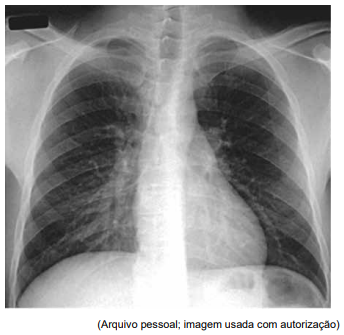

Homem de 53 anos refere quadro de febre e dispneia progressiva há uma semana. Ele tem infecção pelo HIV, mas abandonou o tratamento há cinco anos. Não se sabe a contagem recente de linfócitos CD4 ou a carga viral do HIV. A gasometria arterial revela uma PaO2 de 51 mmHg em ar ambiente. A radiografia de tórax é mostrada a seguir:

Enunciado 4918941-1

O lavado broncoalveolar é positivo para material com coloração de prata metenamina.

Considerando a principal hipótese diagnóstica, constitui o tratamento antimicrobiano mais adequado: